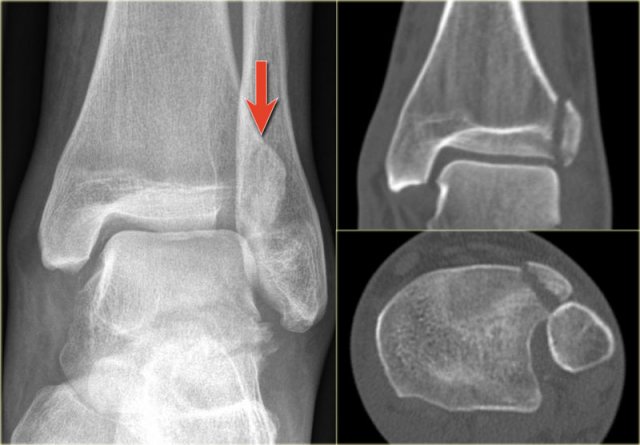

In some cases a fracture of the posterior malleolus is barely or not visible on the radiographs and can only be seen on CT.

First study the radiographs and then continue with the CT.

By the way....there are two fractures.

The CT shows an avulsion of the tertius at the insertion of the posterior syndesmosis (red arrows).

The alignment is so perfect, that you do not see the fracture on the radiographs.

Maybe the fracture is seen on the AP-view as indicated by the red arrows, but this is questionable.

Notice that there is also an avulsion at the tibial insertion of the anterior syndesmosis, i.e. Tillaux fracture.

This combination of findings implicate that the ankle is unstable.

A syndesmotic screw has to be inserted.